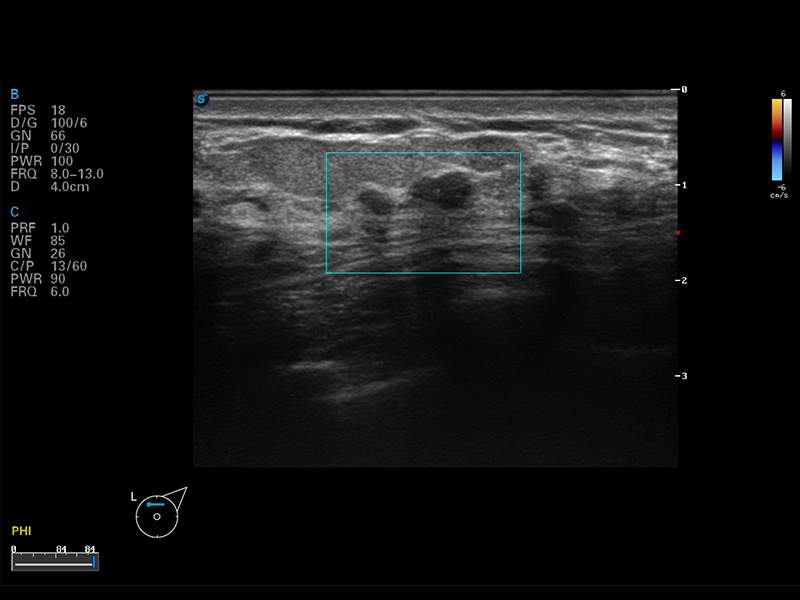

S8 EXP便携式彩色多普勒超声诊断仪是球速体育入口研发的高端全身应用型便携彩超。高通道的VIS平台融合可视化(Visual)、智能化(Intelligent)和人性化(Smart)的特点,配以球速体育入口自主研发生产的探头大家族,使您能够快速、准确的获得病人信息,提高工作效率的同时减轻疲劳。

μ-Scan微米成像